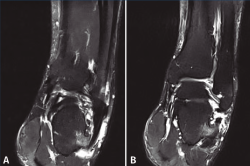

Se realizan los estudios complementarios mediante radiografías, en las que se observa una lesión ósea en la cara lateral del calcáneo con bordes irregulares (Figura 2). La resonancia magnética nuclear informa de “hipertrofia del tubérculo lateral del calcáneo que conlleva severa afectación de los tendones peroneos apreciando signos de tenosinovitis y afectación mayor del tendón peroneo lateral largo con rotura parcial del mismo” (Figuras 3A y 3B). La tomografía computarizada muestra una “exóstosis en cara externa de calcáneo de 12 × 9 × 8 mm” (Figuras 4A y 4B).

Figura 3. Imágenes de resonancia magnética nuclear donde podemos ver la tumoración con edema óseo asociado y tenosinovitis de los tendones peroneos.